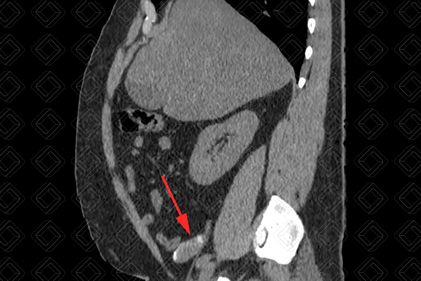

Texto alternativo para a imagem Figuras 1 e 2. Créditos: Dra. Elazir Mota - Rio de Janeiro/RJ

Descrição das figuras 1 e 2: Tomografia computadorizada do abdome; cortes sagital e coronal evidenciando imagem tubular, hipodensa e com calcificação parietal (setas vermelhas), compatível com mucocele de apêndice.

• Tomografia computadorizada do abdome: Em geral, vemos uma lesão tubular, hipodensa, contígua a base do ceco e, em cerca de 50% dos casos, elas contêm calcificações murais (figuras acima). Atenção: Diante da presença de espessamento parietal irregular e nódulos murais, devemos suspeitar de malignidade. Por isso, o exame idealmente deve ser realizado com contraste venoso;